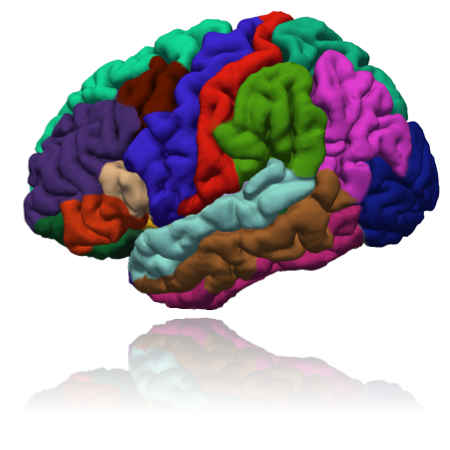

A framework

based on

Freesurfer